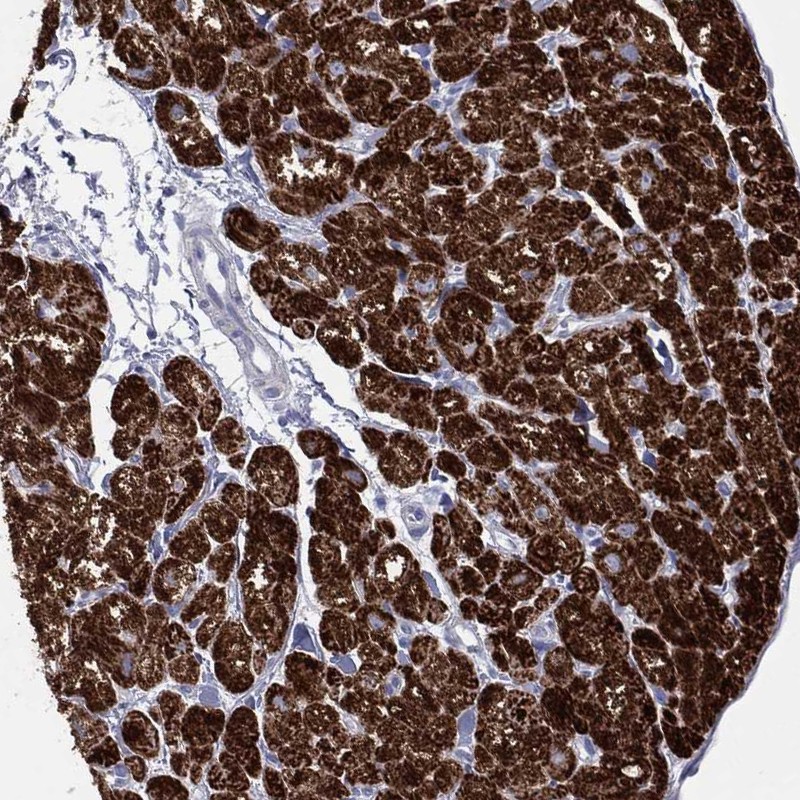

Immunohistochemistry analysis in human heart muscle and fallopian tube tissues using Anti-CPT1B antibody. Corresponding CPT1B RNA-seq data are presented for the same tissues.